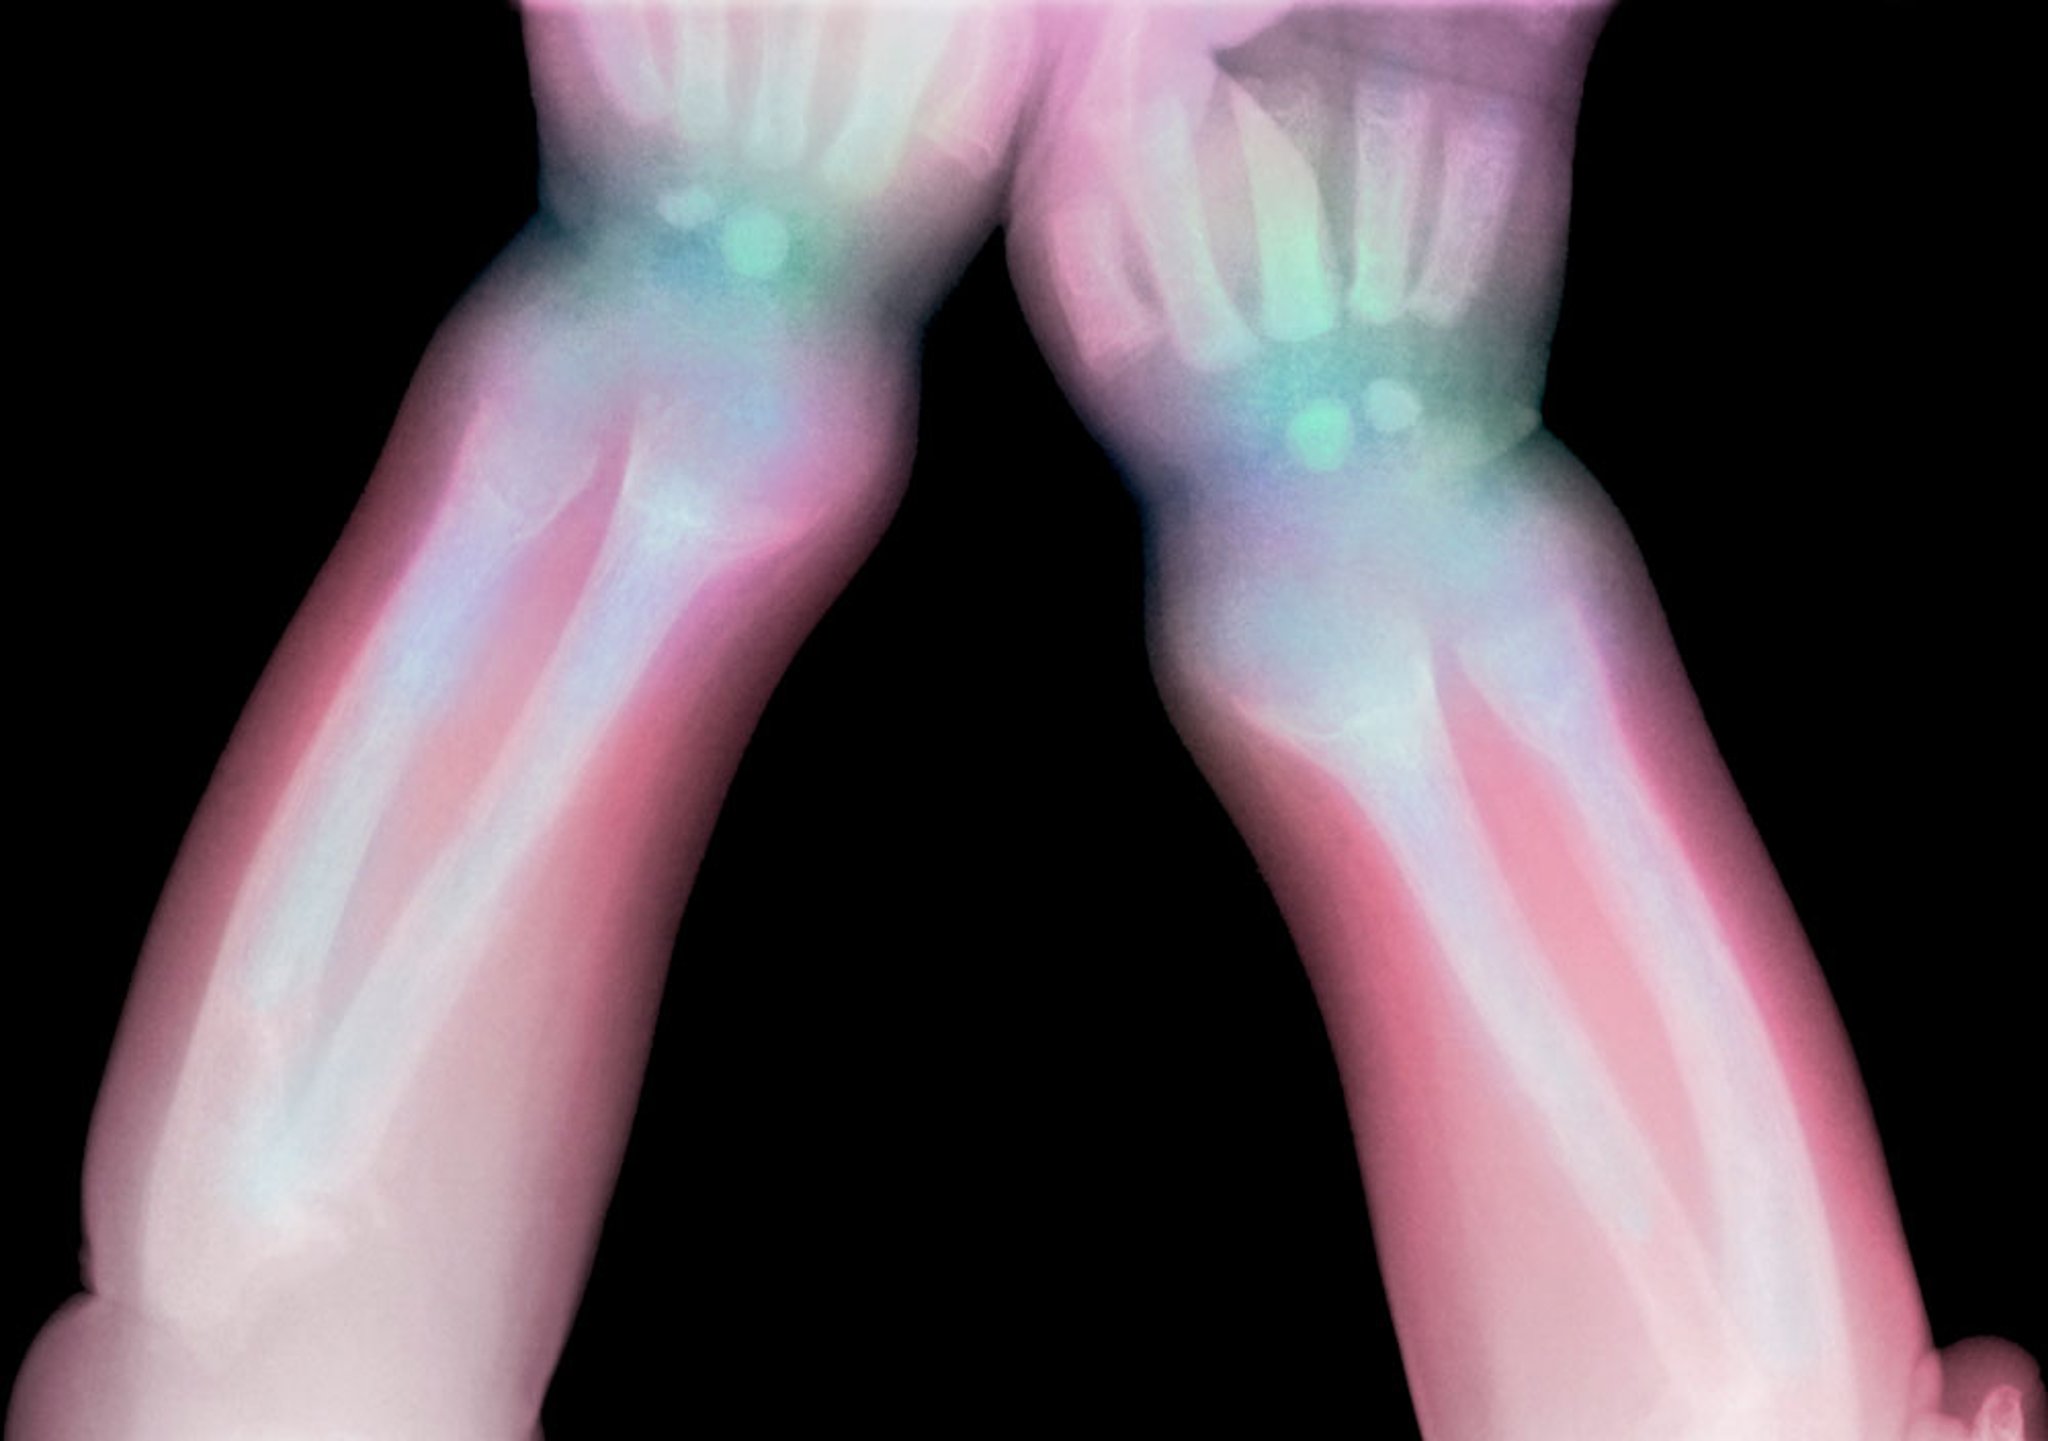

Этот рентгеновский снимок показывает просветление дистальных отделов лучевой и локтевой костей у ребенка с рахитом.